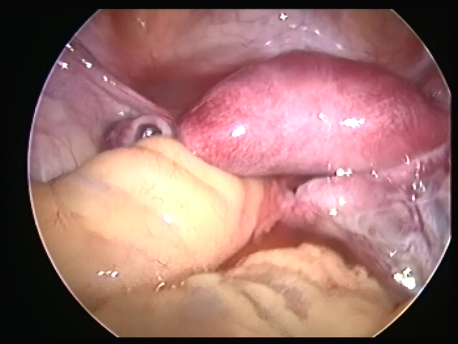

- Infertility and recurrent loss (Subfertility): Infertility means the inability to conceive and recurrent pregnancy loss means loss of 3 or more (in practice, usually 2 or more) consecutive early pregnancy (less than 5 months). Uterine pathology such as abnormal shape (septum or the T shaped uterus), submucous fibroids or polyps, and intrauterine adhesions can cause subfertility. Tubal block due to spasm or mucus plugs can contribute to infertility and can be opened by hysteroscopic cannulation.